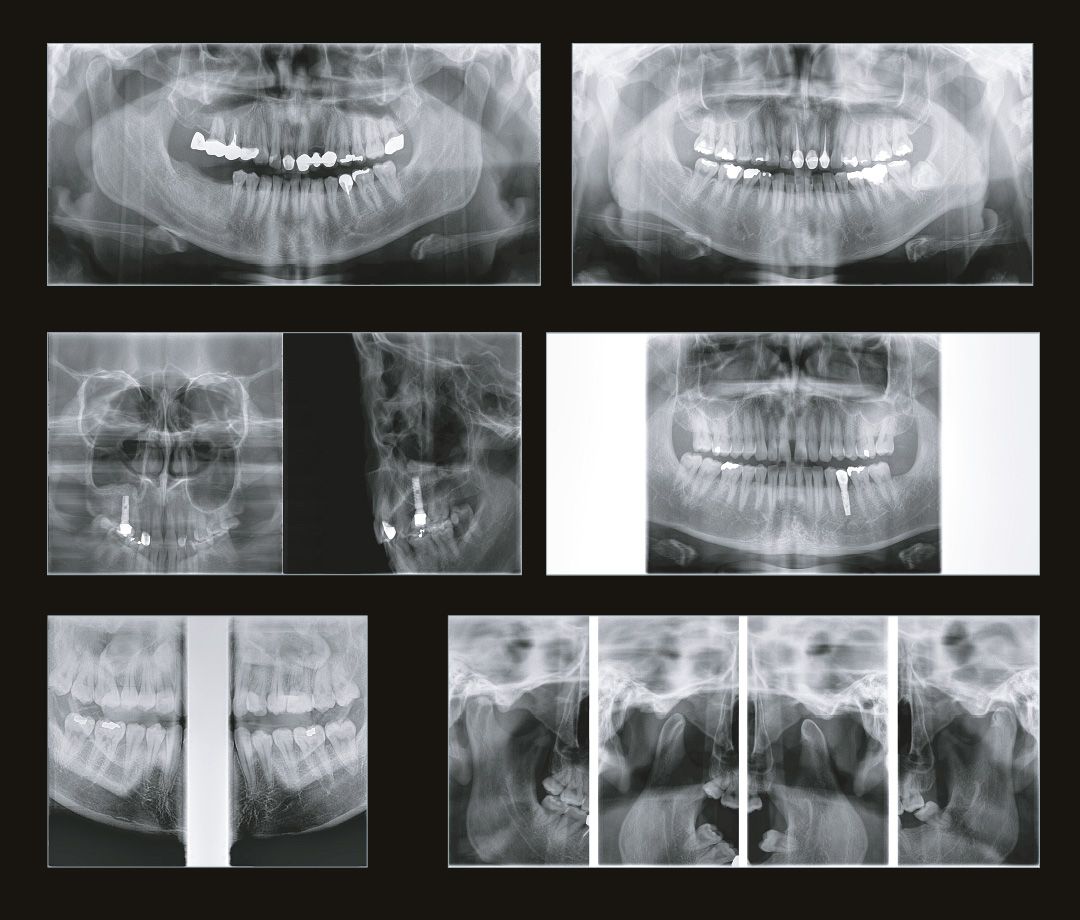

Современная стоматология уже давно не работает вслепую, и каждому из направлений стоматологии необходимо проводить рентгеновские исследования:

Стоматолог-терапевт по снимку видит не только кариес, а также способен оценить, как периодонтальные ткани, так и различные воспалительные процессы затрагивающие пульпарную камеру.

Стоматолог-хирург не способен производить свои манипуляции без снимка КТ, иначе он будет вынужден действовать вслепую, не сумев оценить анатомию области вмешательства.

Стоматолог-ортопед не сможет гарантировать надежность конструкции без правильной оценки стабильности опорных зубов при помощи снимка КТ.

Стоматологу-ортодонту, чтобы правильно простроить план лечения, помимо слепков, так же нужен снимок КТ.

Если же ваша стоматологическая клиника располагается в жилом доме, помимо всего написанного выше, необходимо, чтобы дентальный томограф имел мощность излучения не выше 70кВ. Современные изготовители позаботились и об этом. На рынке представлено несколько моделей, которые удовлетворяют этим требованиям. Например, модель дентального томографа Papaya 3D (Plus) от компании Genoray имеет мощность излучателя 60~69 кВ и может располагаться в жилых помещениях, не принося вред жильцам и удовлетворяя санитарно-эпидемиологическим требованиям.